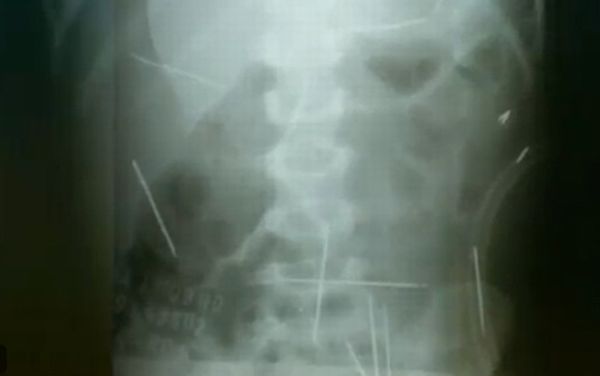

Eles pretendem retirar quatros agulhas do corpo do menino. Duas delas estão no pescoço e outras duas na clavícula, do lado esquerdo. Ainda de acordo com informações do hospital, uma das agulhas estaria perto da medula e poderia colocar a saúde do paciente em risco.

O menino já passou por duas cirurgias para a retirada de objetos do fígado, intestino, bexiga, coração e pulmão. Na sexta-feira (26), ele havia conseguido caminhar com a ajuda de fisioterapeutas do hospital.

O garoto foi levado a uma unidade de saúde de Ibotirama (BA) depois de reclamar de dores na barriga. Um exame mostrou que ele tinha várias agulhas espalhadas pelo corpo. A vítima foi internada em Barreiras (BA) e, depois, transferida para Salvador.